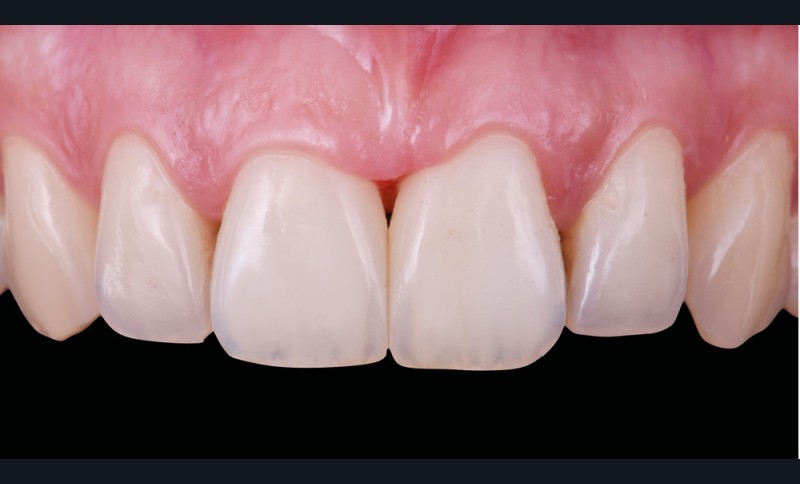

Si les techniques de reconstruction papillaire présentent des résultats non prédictibles, les facettes céramiques peuvent être une réponse fiable au problème des triangles noirs mais imposent une préparation plus marquée. En effet, pour obtenir un profil d’émergence adéquat et une bonne fermeture de l’espace interproximal, il faut préparer les surfaces de contact et venir chercher la ligne de transition palatine, obligeant à retirer une quantité de tissu sain non négligeable.

La fermeture des triangles noirs en technique directe avec des résines composites offre une alternative très favorable avec une approche non invasive, esthétique, un coût réduit et une possibilité de réintervention aisée. Plusieurs méthodes ont été proposées : réalisation à main levée sans matrice (à proscrire), avec bande de matrice transparente plate ou galbée, avec matrice postérieure customisée et utilisée verticalement… Il faut bien comprendre qu’aucun coin en bois ou plastique ne pourra être employé pour stabiliser cette matrice, car il empêcherait la création d’un profil d’émergence anatomique convexe en induisant une déformation concave de la matrice à sa base.